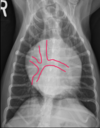

Which structures pair with the times on the “clock face” of the heart in a VD view?

A

11:00 to 1:00: aortic arch

1:00 to 2:00: main pulmonary artery segment

2:30 to 3:00: left auricle

3:00 to 5:00: left ventricle

5:00 to 9:00: right ventricle

9:00 to 11:00: right atrium

9

Q

What is indicated by the white circle in this image?

position of the left atrium

-does not contribute to “clock face”

-between the main stem bronchi